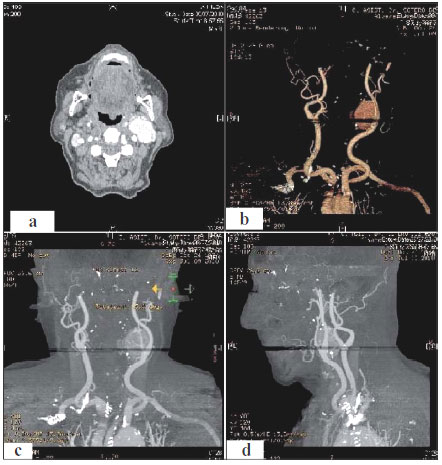

- Garganta: endoscopia fibróptica para examinar la garganta y laringe y posiblemente el esófago y los pulmones, radiografías, TAC, IRM de la cabeza, cuello y pecho, angiograma de cuello para examinar el flujo de los vasos sanguíneos. Estos exámenes son útiles para observar si el cáncer se ha diseminado

- Glándulas salivales: TAC y Imagen por resonancia magnética de cabeza y cuello

- Nasofaringe: examen fibróptico para examinar el tumor en la nasofaringe, un examen neurológico para evaluar el daño en el nervio craneal de la cabeza y el cuello, exámenes de audición, examen dental profundo, radiografías. TAC e Imagen por resonancia magnética de cabeza y cuello y análisis de sangre.

- Cavidades nasales y sinusales: endoscopia fibróptica para examinar el tumor dentro de las cavidades nasales y sinusales, TAC e Imagen por resonancia magnética de la cabeza.

- Laringe: una endoscopia fibróptica de laringe para examinar el área del tumor y determinar si las cuerdas vocales se mueven normalmente, radiografías, TAC, IRM de cabeza y cuello.